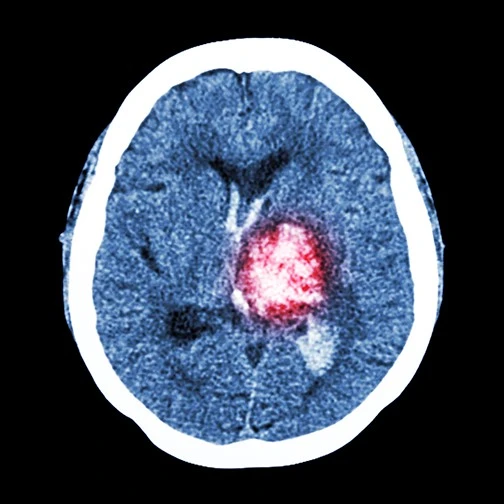

4. Stroke

Because smoking affects your arteries, it can trigger stroke. A stroke happens when the blood supply to your brain is temporarily blocked. Brain cells are deprived of oxygen and start to die. A stroke can cause paralysis, slurred speech, altered brain function and death. Stroke is the fifth leading cause of death in the United States and a leading cause of adult disability.

brain scan stroke